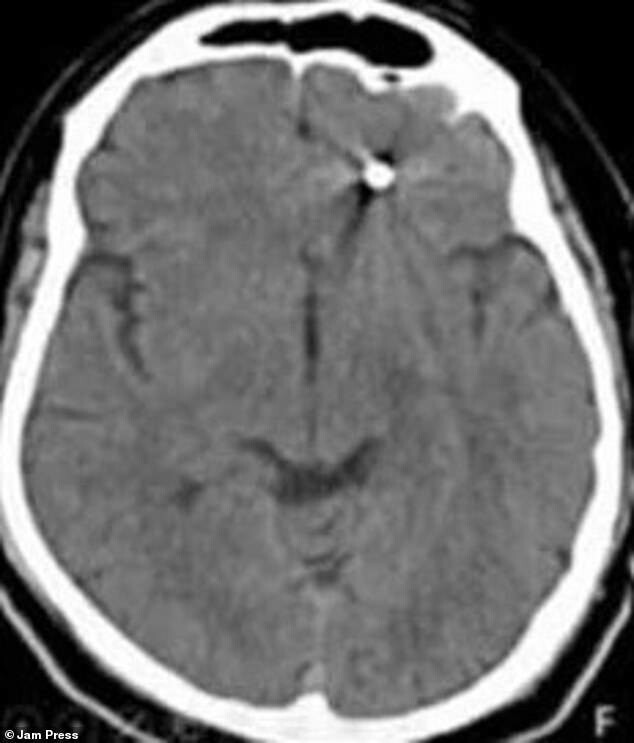

После обследования на томографе выяснилось, что винт вонзился в область, где находится мозг и спинномозговая жидкость. После этого врачи-эксперты собрались и приняли решение о проведении операции».

Операция длилась несколько часов, но хирургам удалось извлечь винт из мозга пациента. Его выписали через несколько дней, и сейчас он идет на поправку.